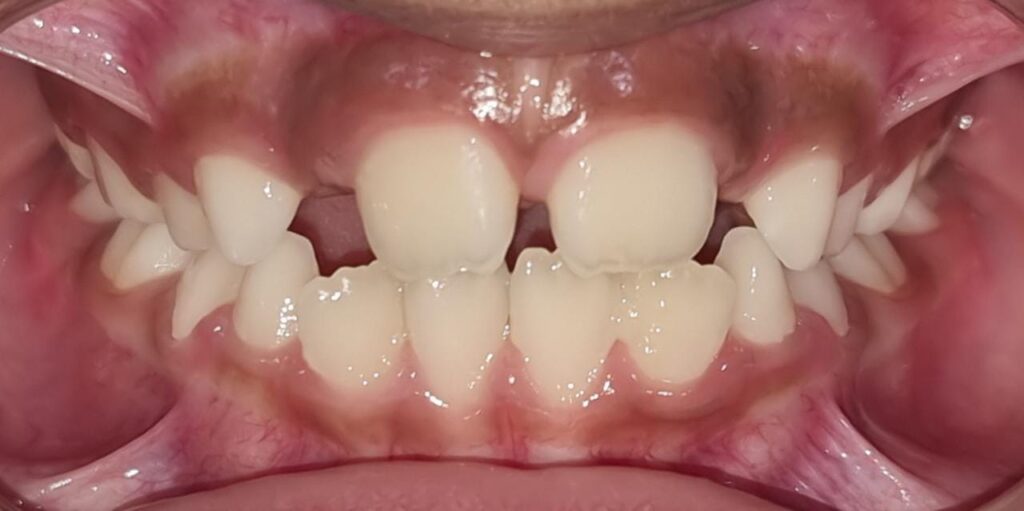

76) Ayyan – Tongue thrust